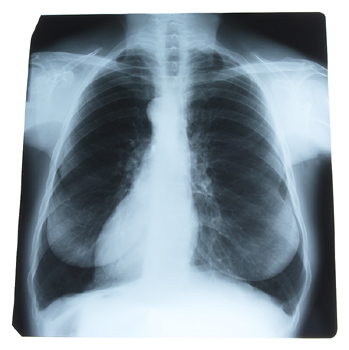

Lung cancer rates among men are on the decline

Results of the most comprehensive analysis to date of the impact of gender differences in lung cancer incidence in the United States indicate that lung cancer rates among men are on the decline, while the rate in women remains steady.Results of the most comprehensive analysis to date of the impact of gender differences in lung cancer incidence in the United States indicate that lung cancer rates among men are on the decline, while the rate in women remains steady.

A new study in the March issue of CHEST, the peer-reviewed journal of the American College of Chest Physicians, shows that, in addition to the unequal incidence of lung cancer in men and women, there are other gender-linked differences, including subtype of lung cancer and survival rate.

"Traditionally, lung cancer has been viewed as a disease of older male smokers, but that is not necessarily the case," said the study's author, Gregory P. Kalemkerian, MD, University of Michigan Medical Center, Ann Arbor, MI. "This data supports the fact that lung cancer is becoming a bigger problem in women every year. If these current trends continue, in 10 to 15 years, the incidence of lung cancer will be identical for women and men."

Researchers from the University of Michigan Medical Center and Wayne State University analyzed data of 228,572 patients (81,843 women and 146,729 men) with lung cancer who were registered in the national, population-based Surveillance, Epidemiology, and End Results (SEER) database between 1974 and 1999. Researchers found that the incidence of lung cancer in men reached a peak in 1984, when 72.5 of every 100,000 men had the disease, then declined to 47 per 100,000 men in 1991. In sharp contrast, the incidence of lung cancer in women continued to rise to a peak with 33.1 per 100,000 women in 1991, and then remained relatively stable at 30.2 to 32.3 per 100,000 women from 1992 to 1999. These variations have resulted in a male/female incidence ratio change from 3.56:1 in 1975 to 1.5:1 in 1999. For both men and women, the median age of diagnosis was 66 years. Women made up 40.9% of patients under the age of 50 but only 35.4% of patients over the age of 50.

"The fact that women appear to be overrepresented among women under the age of 50 is a reflection of increased smoking prevalence among women, especially early in the study period," said Dr. Kalemkerian. "There is still controversy as to whether or not women are more susceptible to tobacco carcinogens, but our findings suggest that women and men are affected differently by their tobacco use. For example, nearly half the women (44.7%) developed adenocarcioma, while the men were most likely to develop squamous cell carcinoma (36.3%)."

The study also found that women had significantly higher rates of survival at every stage of the disease. From 1975 to 1987, the five-year survival rate was 12.1% greater in women than in men, and, from 1988 to 1999, women's five- year survival rate was 6.5% higher. Even when researchers compared the survival of early-stage patients who all underwent surgery, they found that after two years, 74.3% of women survived, compared to 66.0% of men, and, after five years, 56.8% of women survived, compared to only 48.3% of men. Researchers speculate that the difference in survival can be attributed to men having more frequent comorbid conditions, such as heart disease or severe emphysema. Aside from the stage of disease, being a man was the factor that most negatively impacted survival among patients.

"Lung cancer is the leading cause of cancer-related mortality for women in the United States," said Paul A. Kvale, MD, FCCP, President of the American College of Chest Physicians. "Although it used to be considered a male smoker disease, this shortening gender gap clearly illustrates a behavior shift over recent years in women. This study reinforces the need for physicians to focus on women who are susceptible to lung cancer."